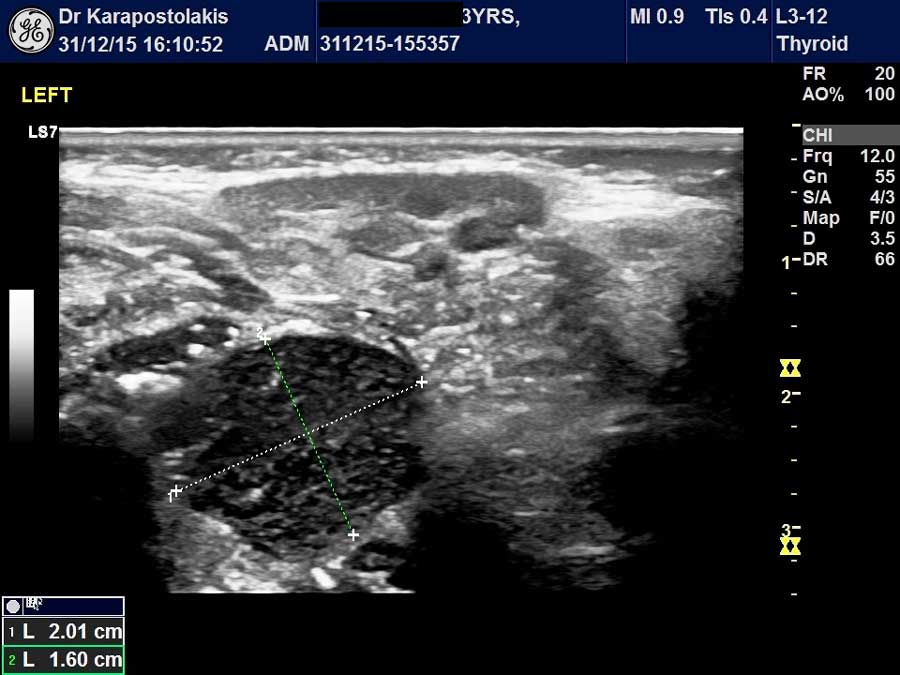

- Υπερηχογράφημα θυρεοειδούς αδένα και παραθυρεοειδών αδένων

Στο Ιατρείο Υπερήχων Παιδιών & Ενηλίκων χρησιμοποιείται η Ελαστογραφία (SE) στη μελέτη:

- όζων θυρεοειδούς,

- λεμφαδένων,

Γενικά η Ελαστογραφία χρησιμοποιείται ως συμπληρωματικό «εργαλείο» στον υπερηχογραφικό έλεγχο όλο και περισσότερο τα τελευταία χρόνια. Η ειδικότητα της μεθόδου εξαρτάται από την εμπειρία του εξεταστή.

Στο Ιατρείο Υπερήχων Παιδιών & Ενηλίκων λόγω της συνεργασίας με διεθνούς φήμης και κύρους κυτταρολόγο έχουμε τη δυνατότητα να ταυτοποιούμε σχεδόν καθημερινά τα αποτελέσματα της ελαστογραφικής μελέτης με το κυτταρολογικό έλεγχο σε περιστατικά όπου πραγματοποιείται FNA. Η εμπειρία αυτή μας επιτρέπει να βελτιώνουμε συνεχώς τη μεθοδολογία μας αυξάνοντας παράλληλα την ευαισθησία και την ειδικότητα της Ελαστογραφίας.